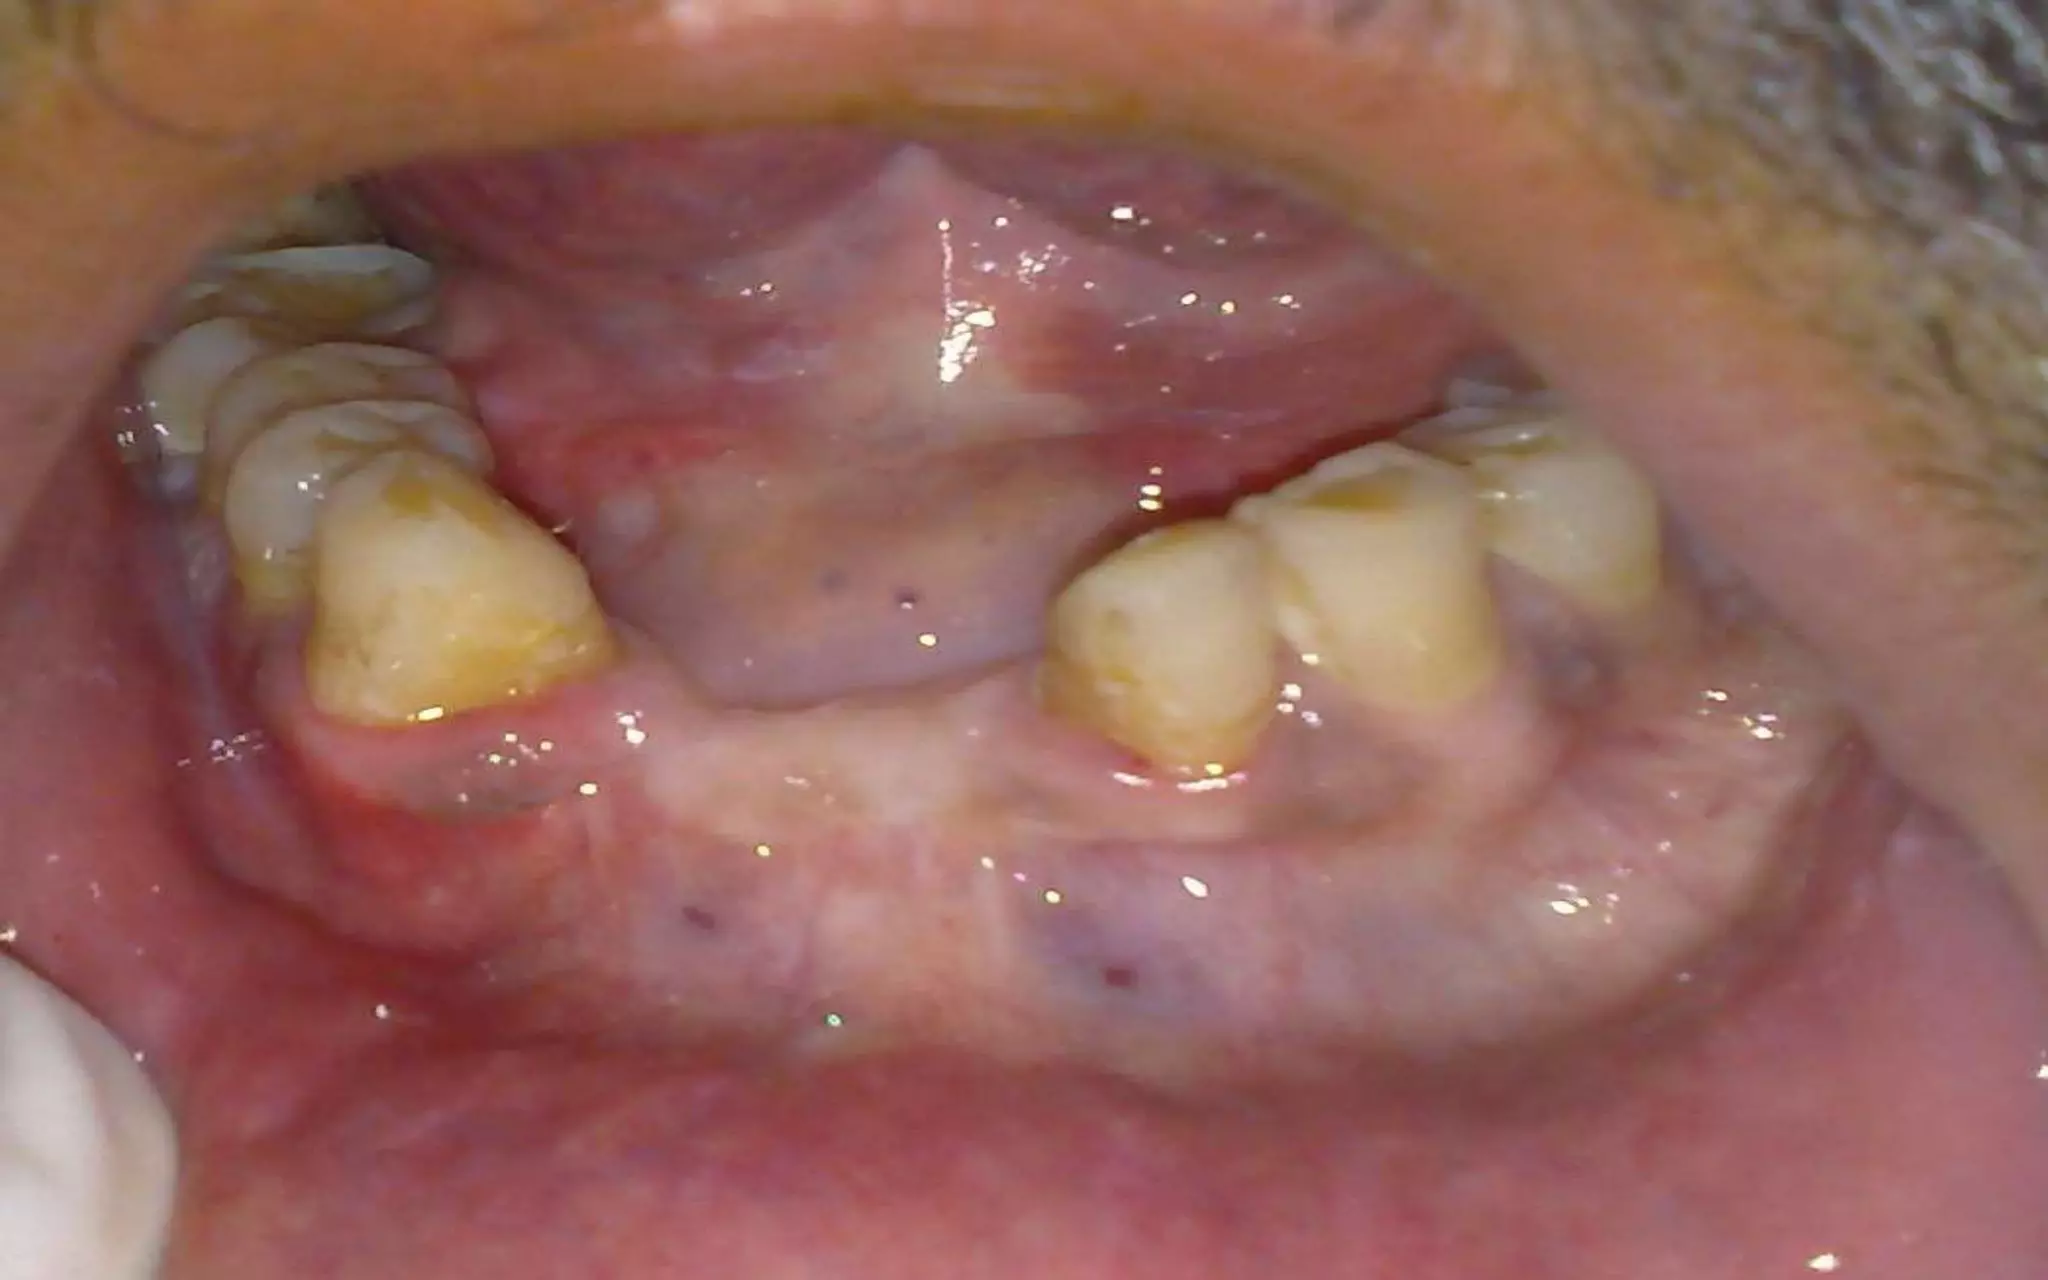

What are the consequences of tooth loss?

But most important consequence is

loss of self confidence… self embarassment

Best solution is dental implants